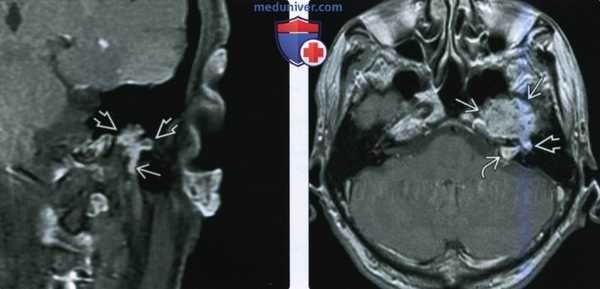

(Слева) При корональной МРТ Т1 ВИ С+ FS у пациента с кондуктивной тугоухостью и подергиванием мышц лица определяется мультифокальная контрастирующаяся ШЛН, проникающая в ячейки сосцевидного отростка и книзу вдоль сосцевидного сегмента ЧH VII.

(Справа) При аксиальной МРТ Т1 С+ визуализируется контрастирующееся образование, выбухающее в медиальные отделы средней черепной ямки из большого поверхноаного каменистого нерва. Диагноз ШЛН можно заподозрить при распространении по ходу барабанного и лабиринтного ЧН VII во внутренний слуховой канал.